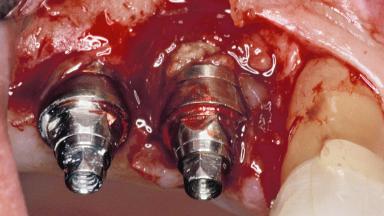

A 72-year-old female patient was referred to the specialist clinic with signs of peri-implantitis associated with implant 14. Two implants (sites 14 and 15) had been in function for three years. The patient was in good general health and was not taking any medication. She was a former smoker (12–15 cigarettes a day for 50 years) but had ceased smoking two years prior to implant placement. Her periodontal condition was stable, with no probing depths above 5 mm and a full-mouth plaque score (FMPS) of 35%.